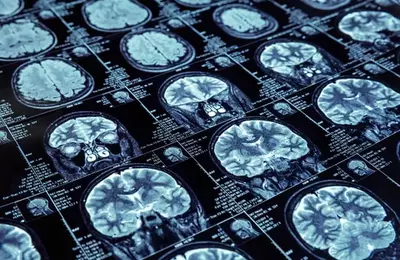

مستشفى شيراز المركزي - ام. ار. اي

التصوير بالرنين المغناطيسي